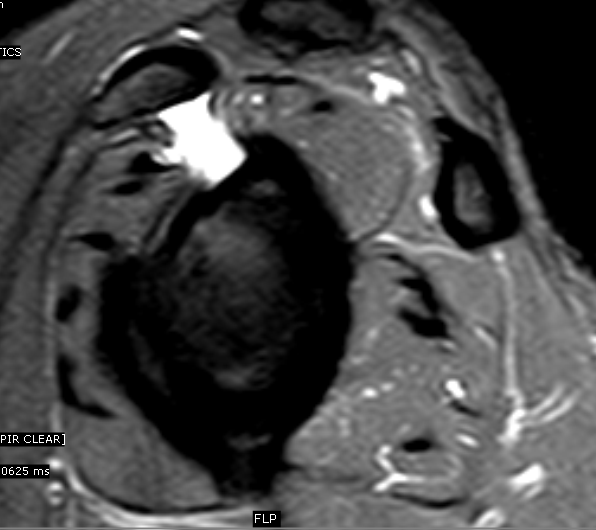

SubcoracoidSubscapularis Bursa MRI Sumer's Radiology Blog Scapular Bursitis Mri Web mri in snapping scapula syndrome, which is a clinical diagnosis, exquisitely reveals soft tissue changes. Finally, an mri can be used to. Web scapulothoracic bursae refer to a number of bursae that allow for the gliding movement of the scapulothoracic joint. Web they discovered bony incongruity in 26 of 26 scapulae. Web more recently, mri and ultrasound have been. Scapular Bursitis Mri.

SubcoracoidSubscapularis Bursa MRI Sumer's Radiology Blog Scapular Bursitis Mri Web scapulothoracic bursitis refers to inflammation of the bursae secondary to trauma or overuse owing to sports. Web they discovered bony incongruity in 26 of 26 scapulae. Web mri in snapping scapula syndrome, which is a clinical diagnosis, exquisitely reveals soft tissue changes. Web the initial treatment of scapulothoracic bursitis and scapulothoracic crepitus should be nonoperative. Web scapulothoracic bursae refer. Scapular Bursitis Mri.